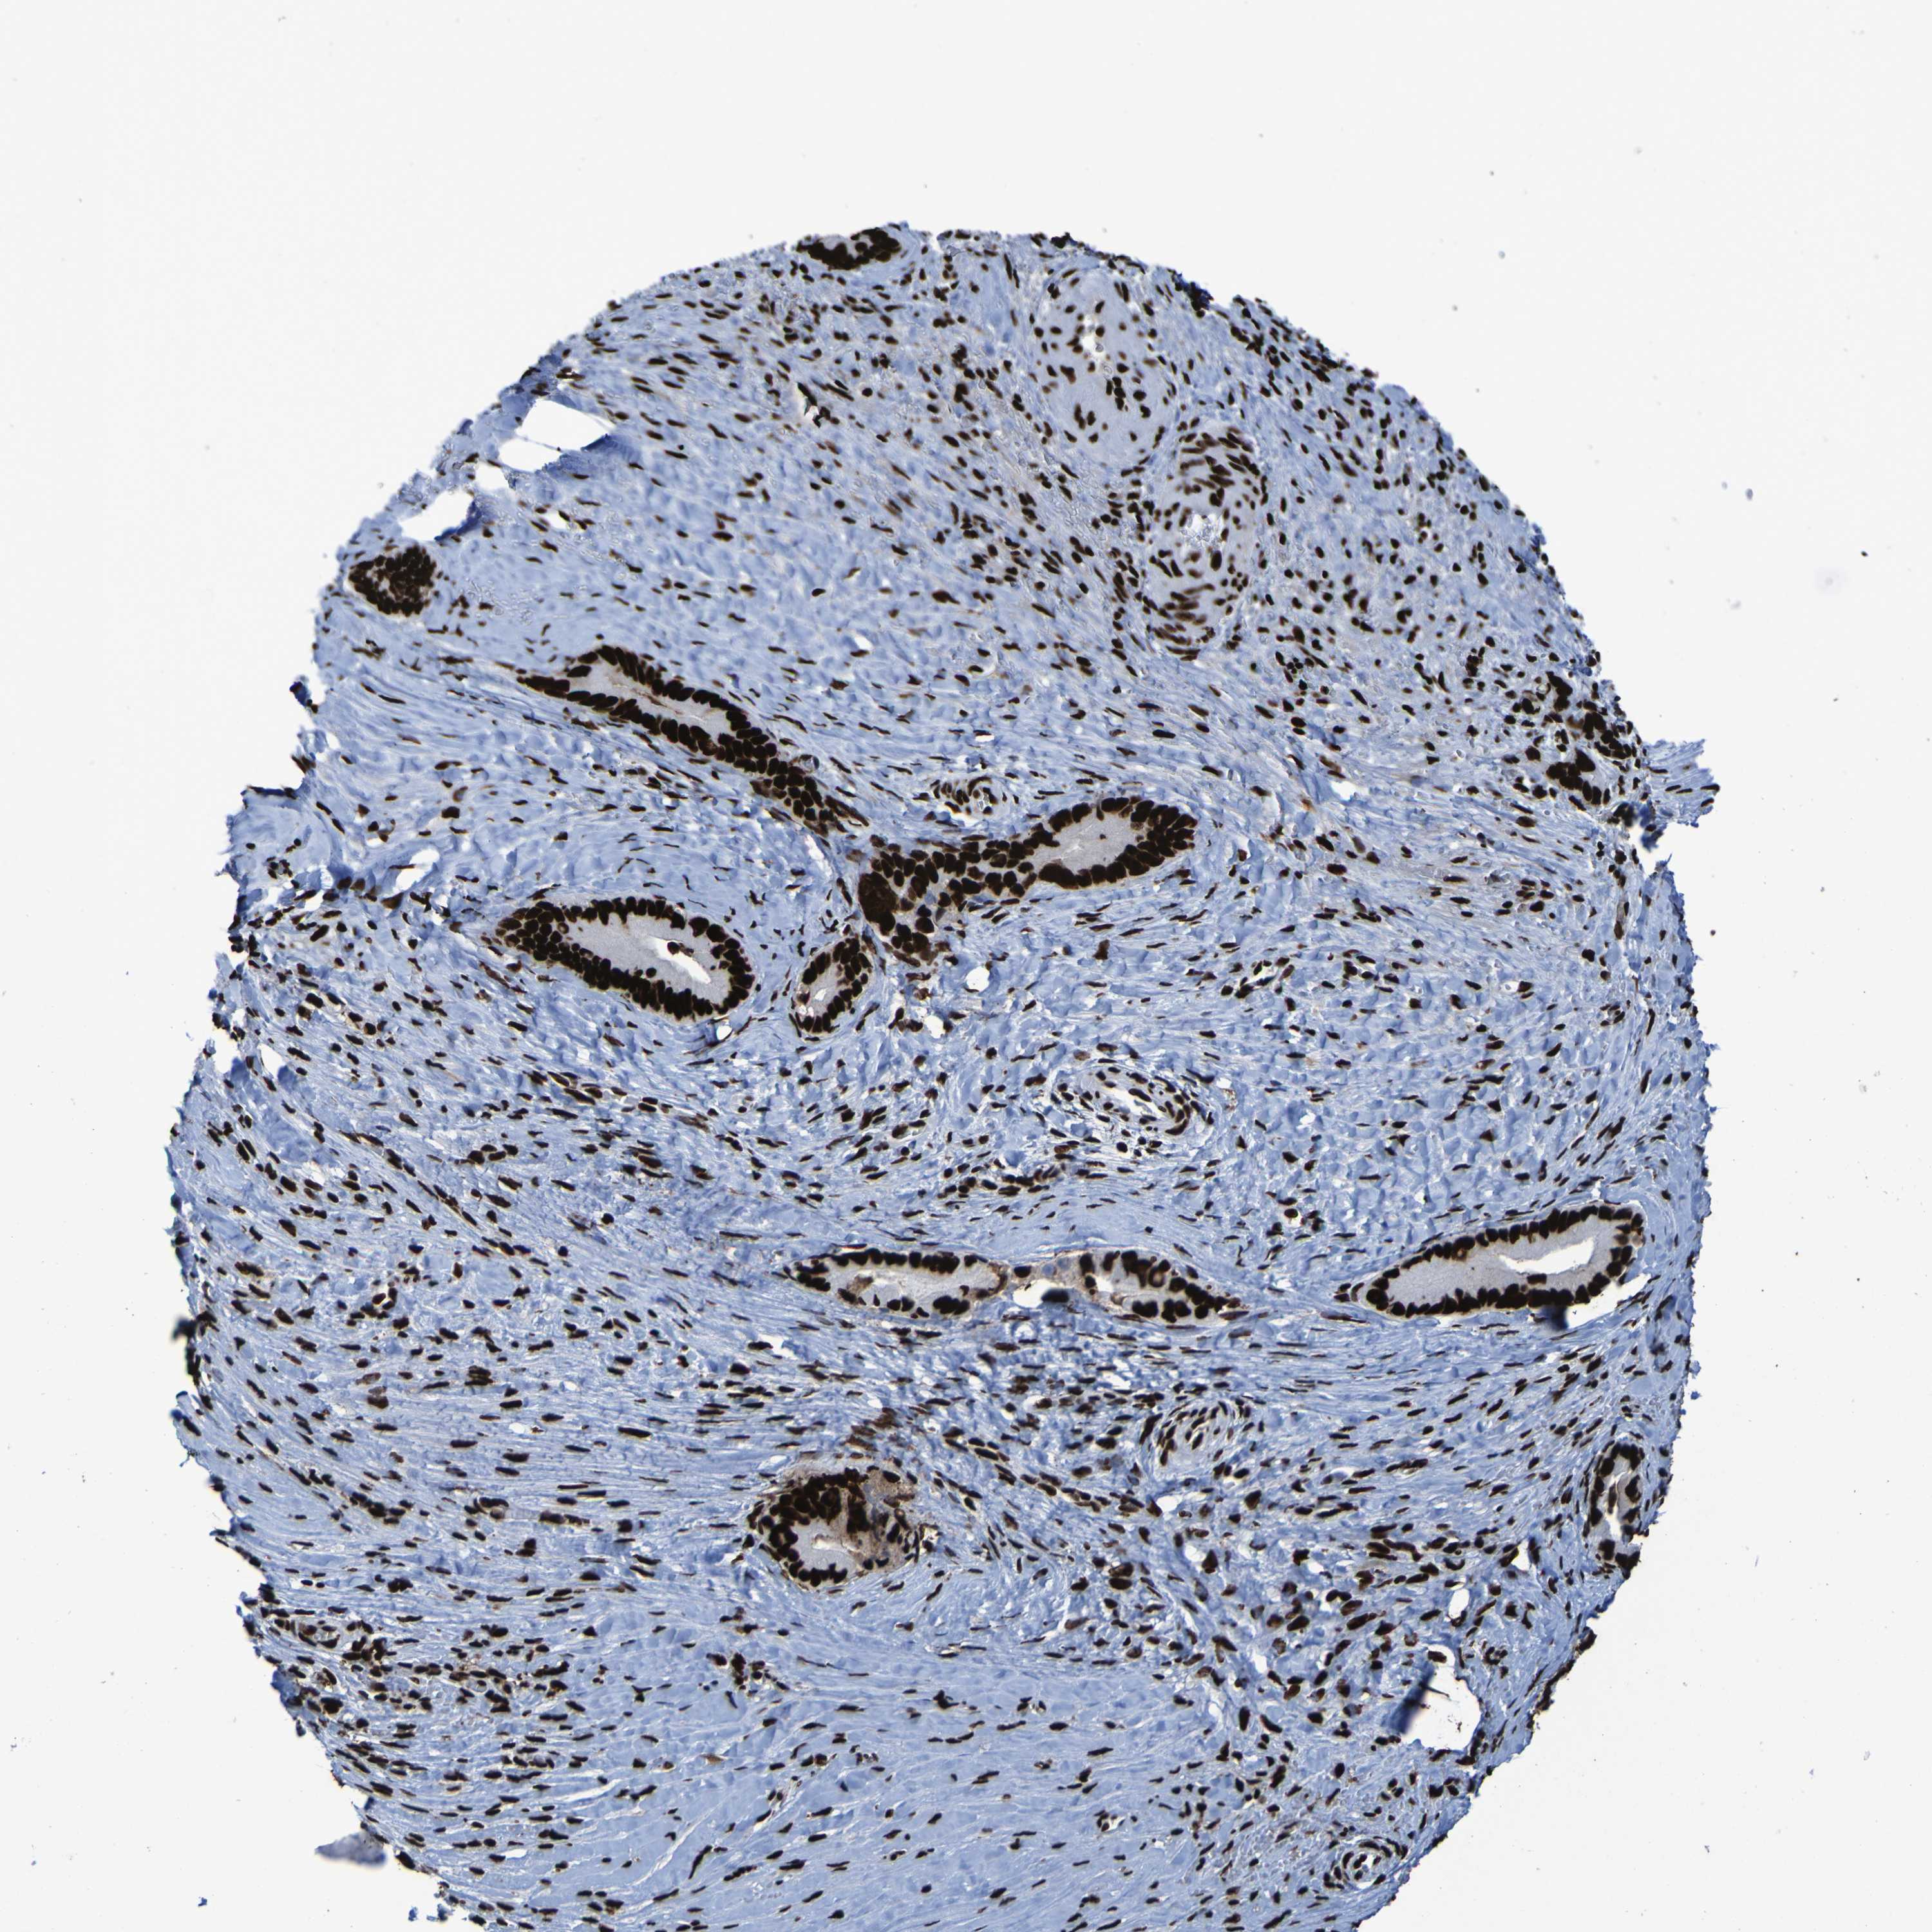

LIVER CANCER - Protein expressioni

A mouse-over function shows sample information and annotation data. Click on an image to view it in a full screen mode. Samples can be filtered based on level of antibody staining by selecting one or several of the following categories: high, medium, low and not detected. The assay and annotation is described here.

Antibody stainingi

Antibody staining in the annotated cell types in the current human tissue is reported as not detected, low, medium, or high, based on conventional immunohistochemistry profiling in selected tissues. This score is based on the combination of the staining intensity and fraction of stained cells.

Each image is clickable and will lead to virtual microscopy that enables deeper exploration of all samples and also displays staining intensity scores, fraction scores and subcellular localization as well as patient and tissue information for each sample.

Antibody HPA011384

Antibody CAB012983

Staining

High

Medium

Low

Not detected

Intensity

Strong

Moderate

Weak

Negative

Quantity

>75%

75%-25%

<25%

None

Location

Nuclear

Cytoplasmic/membranous

Cytoplasmic/membranous,nuclear

Cholangiocarcinoma

Carcinoma, Hepatocellular, NOS